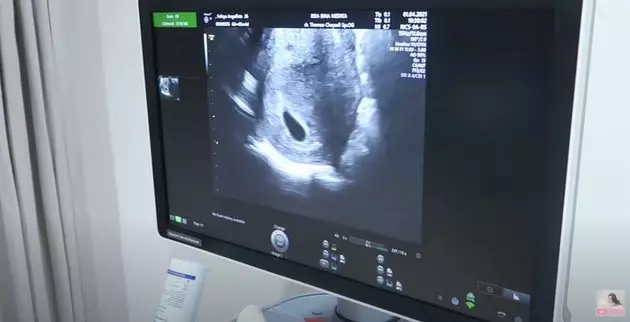

7. Momen USG sang bayi adalah salah satu momen yang sangat menyenangkan untuk kedua pasangan muda ini.

foto: YouTube/FELITOgether